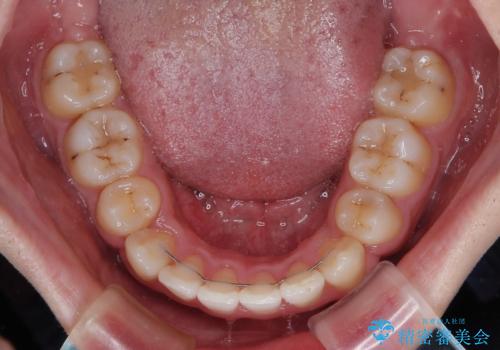

上下の八重歯とクロスバイト ワイヤー装置での抜歯矯正

前歯の歯列が整ったことで、歯磨きが大変やりやすくなり、患者様には大変満足していただけました。